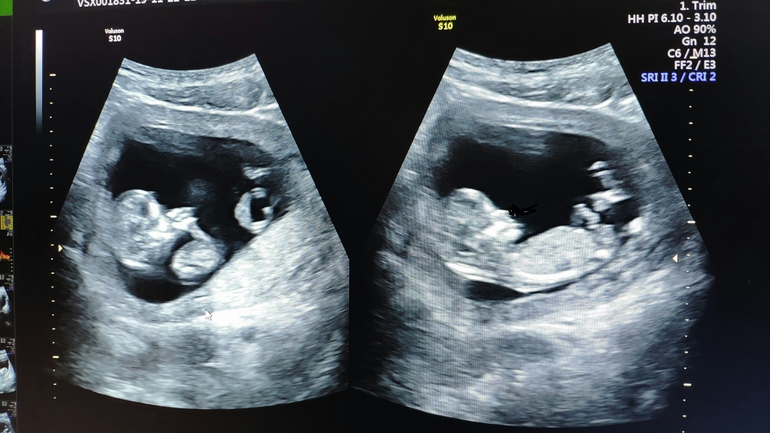

Время летит молниеносно, вчера ещё было две полоски, а сегодня я увидела настоящего человека на мониторе УЗИ.

УЗИ. Чтоб вы понимали, то это ЖК, где врач с суровым лицом сухо диктует цифры медсестре, из которых ты пытаешься понять хоть что-то. Благодаря невнимательности Медсестры я узнала КТР - 64 мм😍 Моё напряжение нарастало. И тут: всё хорошо, малыш соответствует нормам, органы на месте, срок 12+4, пдр 29 мая. И мне показали экран, божечки, этот человечек машет ручкой! Мой человечек! 😍 Тут эмоции захватили 🥰 В этот момент я была счастлива!

Ещё час я разглядывала свою букашку на фото, забыв про жуткий голод.